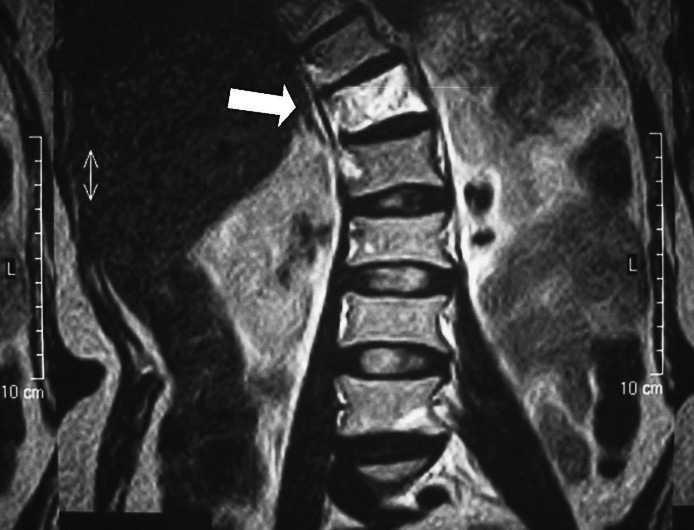

Медицинские иллюстрации и рентгеновские снимки гемангиомы позвоночника